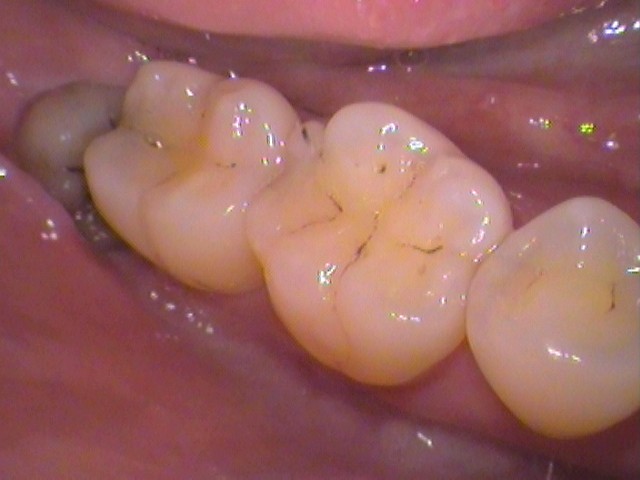

お口の中を見てみると、

このような状態。

親知らずがひょっこり顔を出しているのが分かりますね。

ここです。